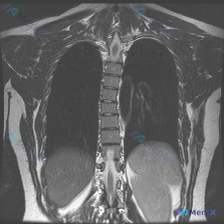

整理到一份临床诉求指向「脊柱侧弯」的病例资料: 仅有的影像检查是胸部MRI冠状位T2加权像,影像报告的核心发现是: - 双侧肺野、纵隔、心影未见明显局灶性病变或占位; - 胸椎序列清晰,椎体形态基本正常,未见明显的形态异常或骨质信号改变; - 双侧胸廓、软组织结构大致对称。 但结合「脊柱侧弯」的核心...